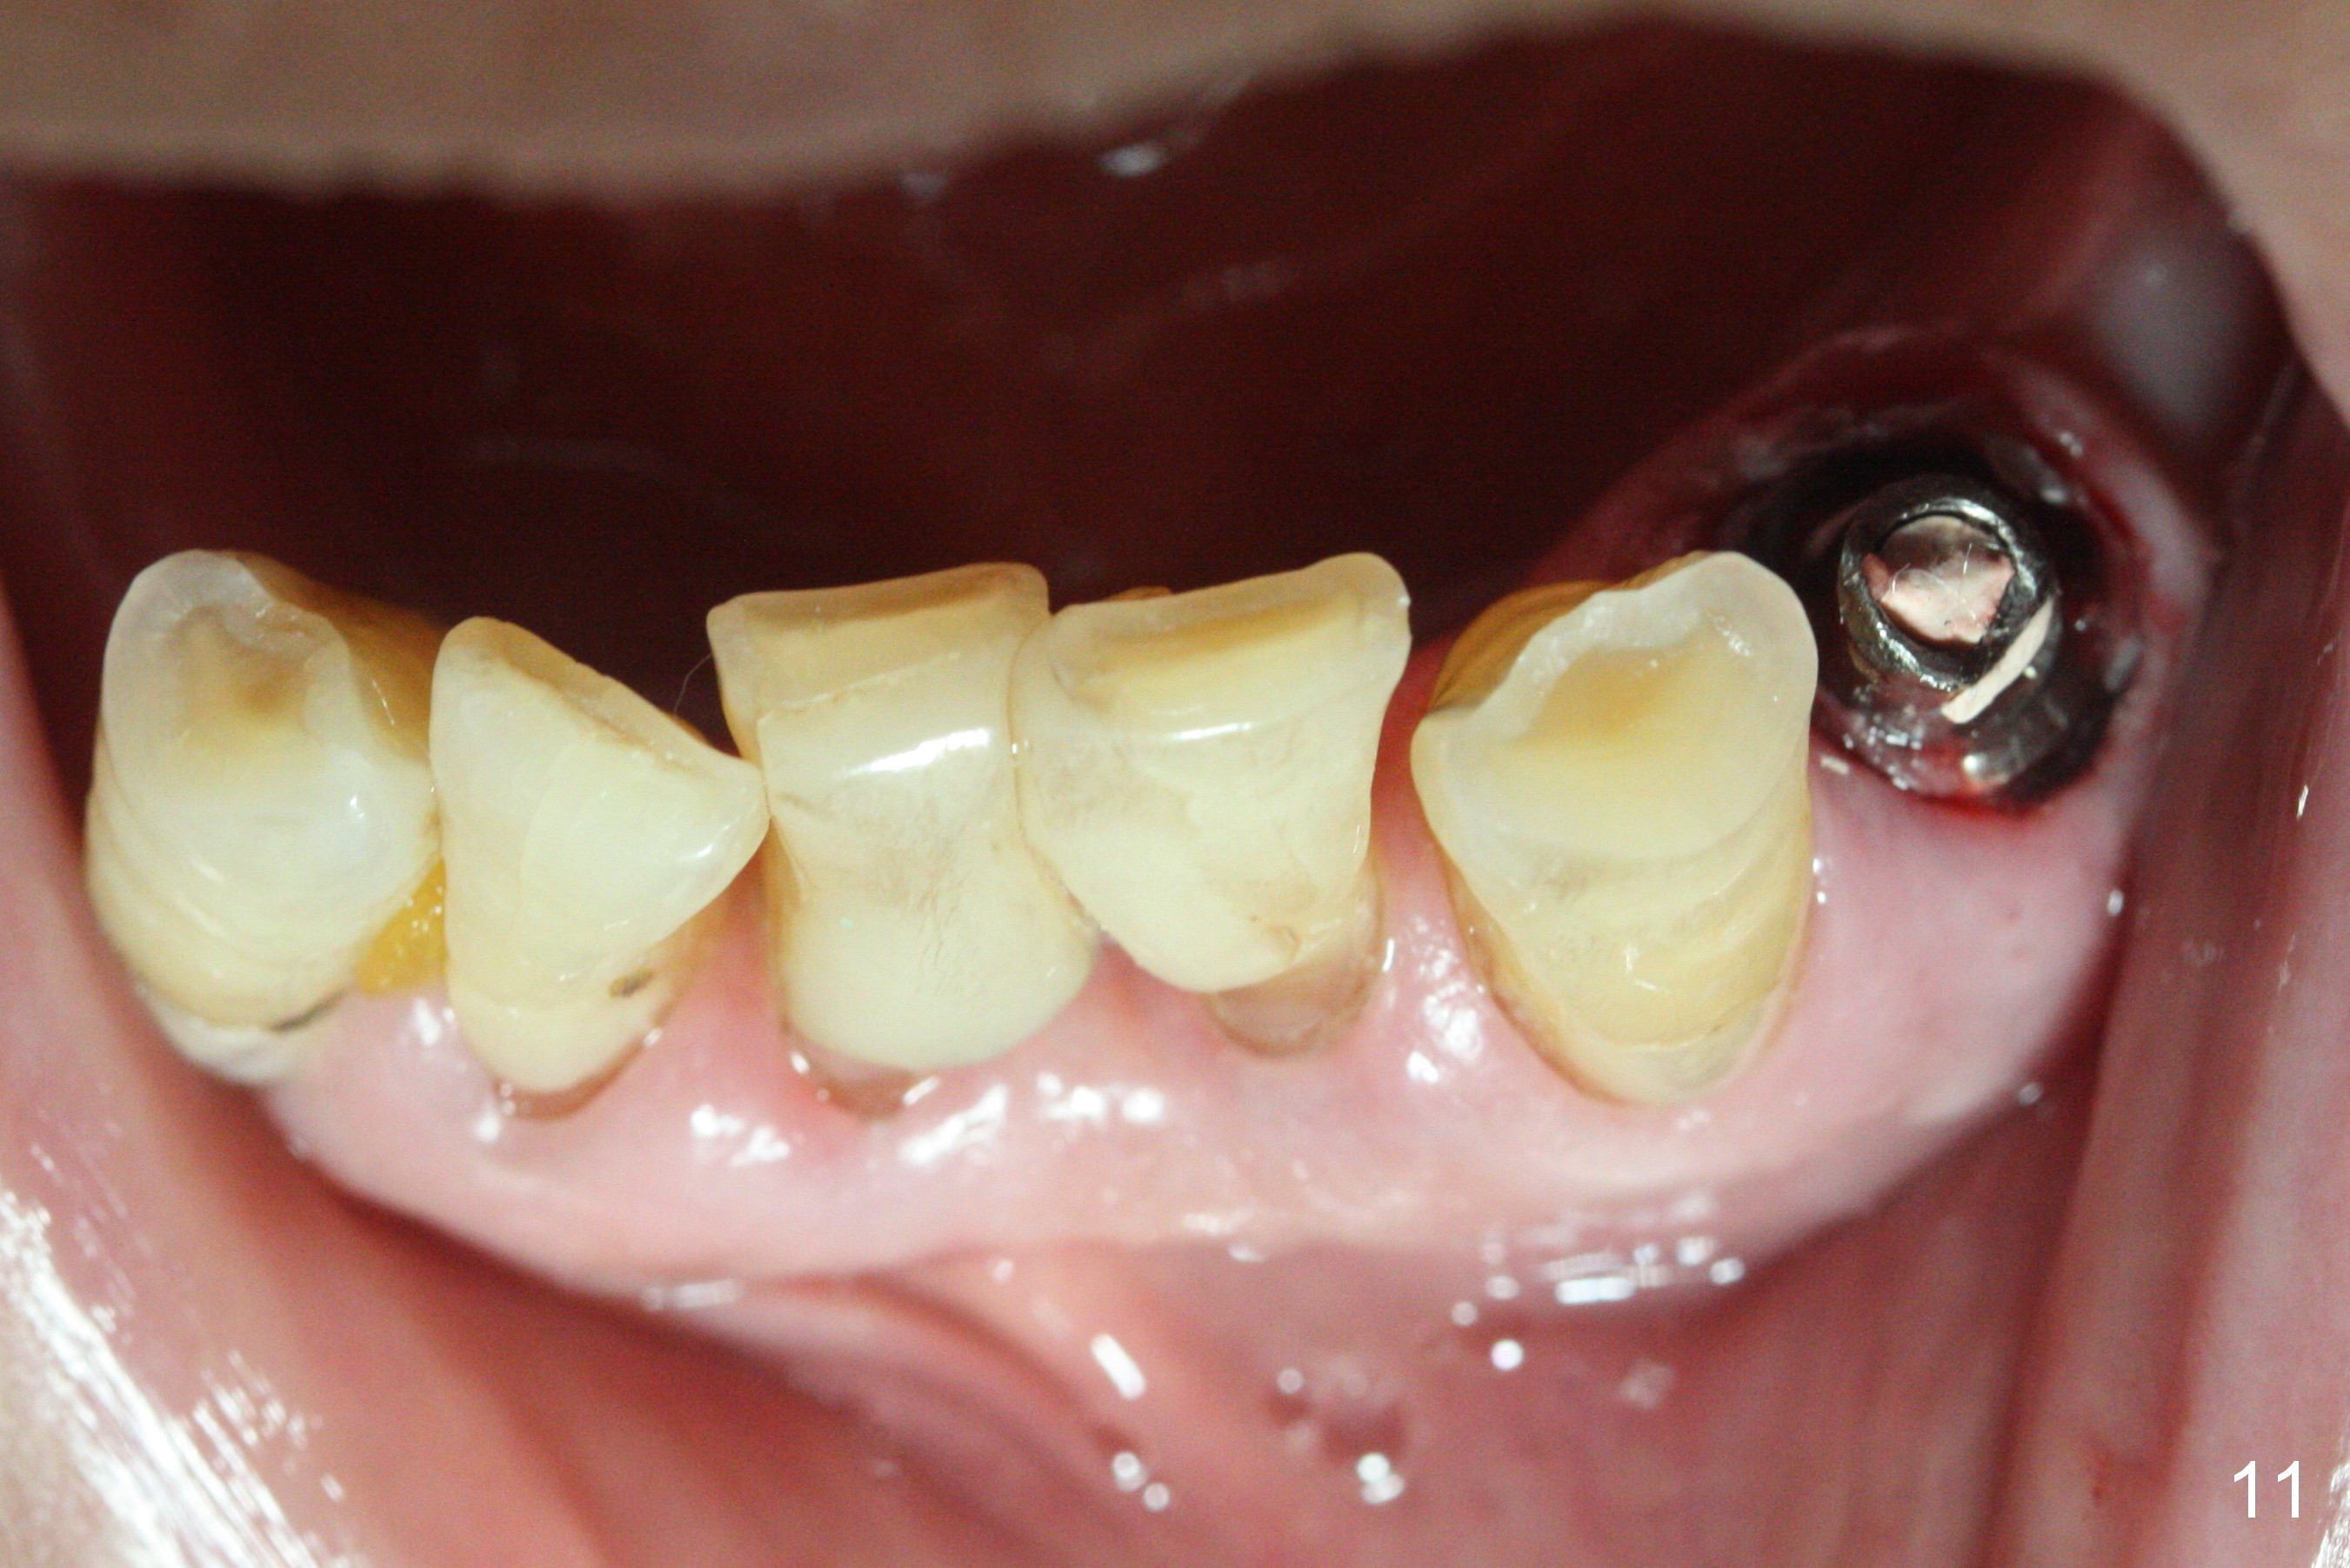

The patient returns 2 days postop because of hemorrhage (Fig.10,11 * after removal of loose periodontal dressing). Periodontal dressing is repacked (Fig.12). The hemorrhage may be due to incomplete removal of granulation tissue or invasion of the Incisive vessel intraoperatively, although there is no pain or paresthesia postop. Soft food is recommended without the upper complete denture. A provisional is fabricated (Fig.14 P) nearly 3 months postop (after changing the 5.5x5(5) mm abutment to 4.5x5(4) mm, Fig.13) when an implant is being place is #31.